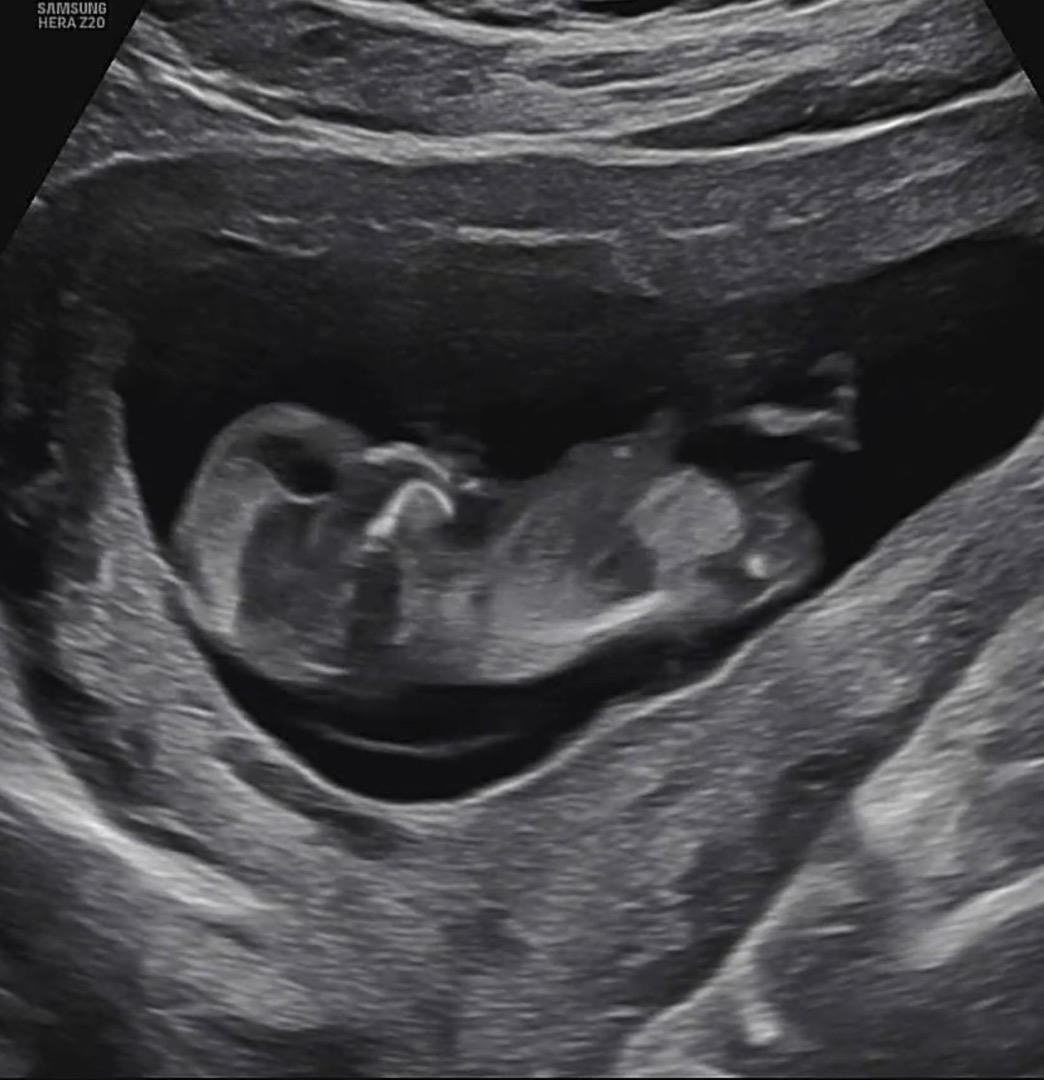

드디어 각도법을 볼수있는 12주차가 되었네요 혹시 각도법 잘보시는분들 성별 추측부탁드려요💙🧡

저게 성기가 맞다면 딸 같아욧